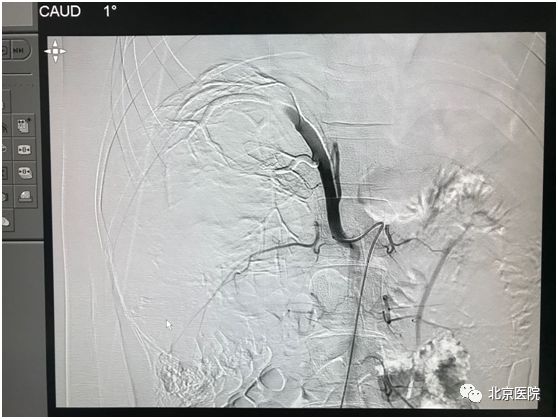

北京医院肿瘤微创治疗中心李晓光团队借助DSA影像技术,经股动脉局麻穿刺置管,利用介入手段对患侧肾动脉选择性造影,证实肿瘤供血动脉、肿瘤生长部位、大小、有无动静脉瘘,再利用超选技术确定目标血管行肾动脉栓塞术。次日该患者如期行“右肾癌根治术”。手术顺利,术中出血量少量,达到预期效果。

肿瘤染色

栓塞后可见肿瘤供血主干呈枯树枝样